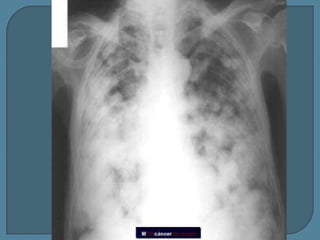

Metástasis de Ca. de colon

Metástasis de Ca. de ovario